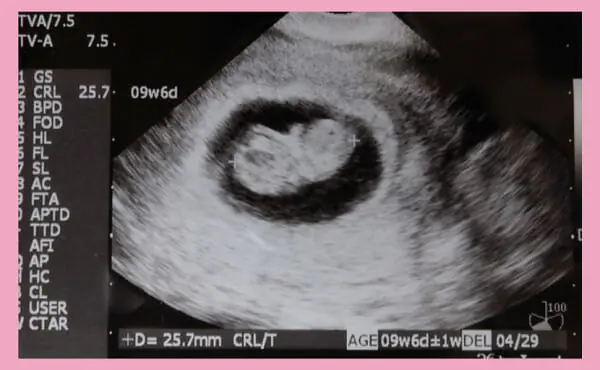

怀孕第9周的宝宝大小(胎儿头臀长:CRL)是20~30mm,胎囊(GS)是5.7cm,体重是1~3g左右。正好是1个草莓的大小。胎儿已经长成人形,头与身体被一个断口区隔开。是脸与手、脚趾等细小部位也一点一点长出来的时期。此外,生殖器开始发育也是在怀孕第9周左右时。

另外,胎儿心跳最快的时候是在怀孕第9周。胎儿心跳在怀孕第5周时为90~100次/分钟左右,大多都是在这个时期透过B超(超声波检查)第一次确认到心跳。心律在怀孕第9周之前稳步增加,并在怀孕第9周中期达到170~180次/分钟的峰直。之后随着怀孕週数的推进,胎儿心律逐渐减少,在怀孕第16周左右稳定在150次/分钟左右,直到分娩当天。

是怀孕第9周的超声波照片。